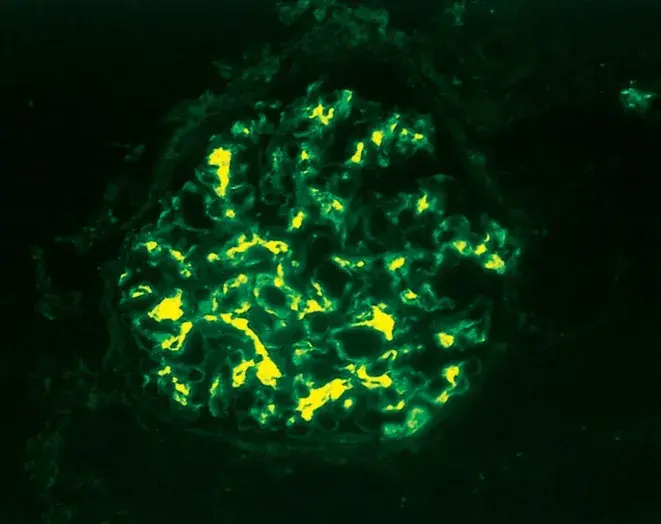

Injúria Renal Aguda (revisão Lancet 2025)

Injúria Renal Aguda (revisão Lancet 2025)